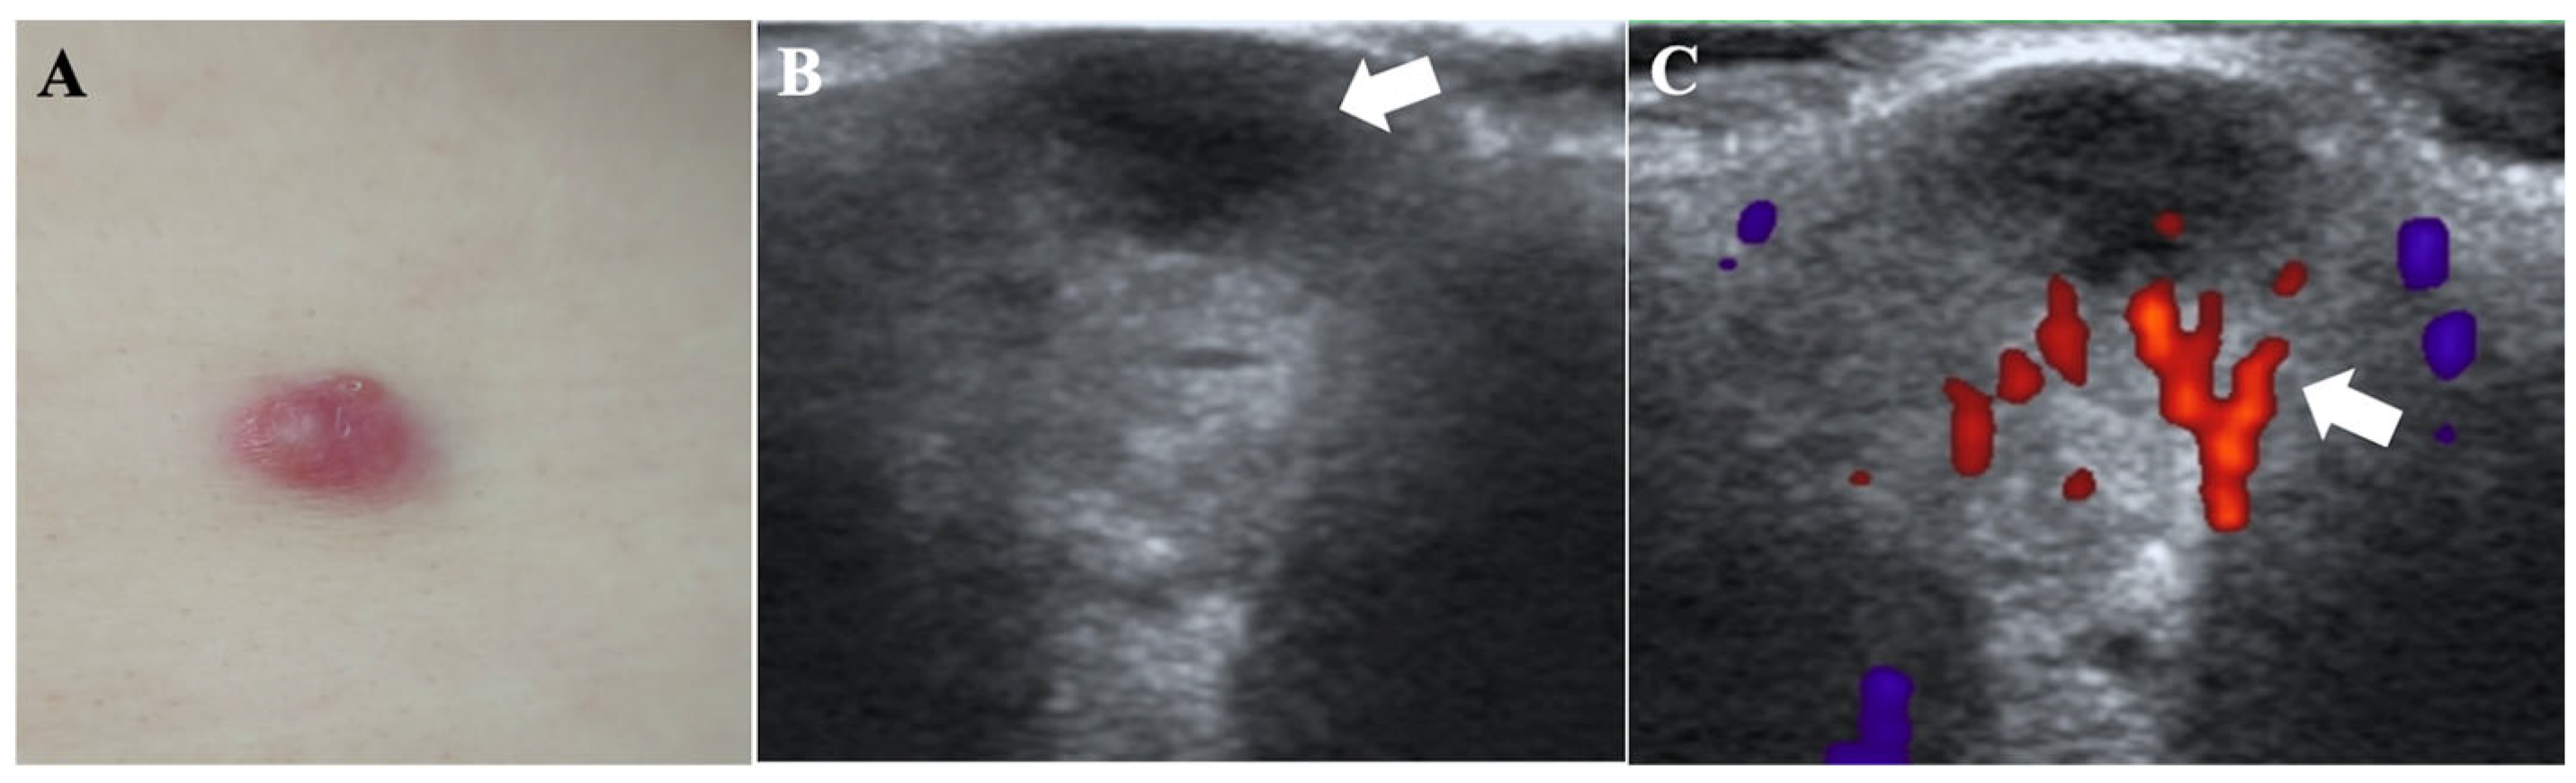

2.2.2. Imaging Studies

| Physical examination | an irregular, dark red plaque with multiple firm, smooth-surfaced nodules | a dark red, firm, freely mobile nodule with a smooth surface | several mobile, firm, subcutaneous nodules with smooth surfaces |

| HFUS features at presentation | |||

| Regular shape | − | + | + |

| Well-defined borders | − | − | + |

| Echogenicity | hypoechoic | hypoechoic | hypoechoic |

| Involvement layers | epidermis, dermis and subcutaneous tissue | dermis | subcutis |

| CDFI features at presentation | |||

| Abundant vascularity | + | − | − |